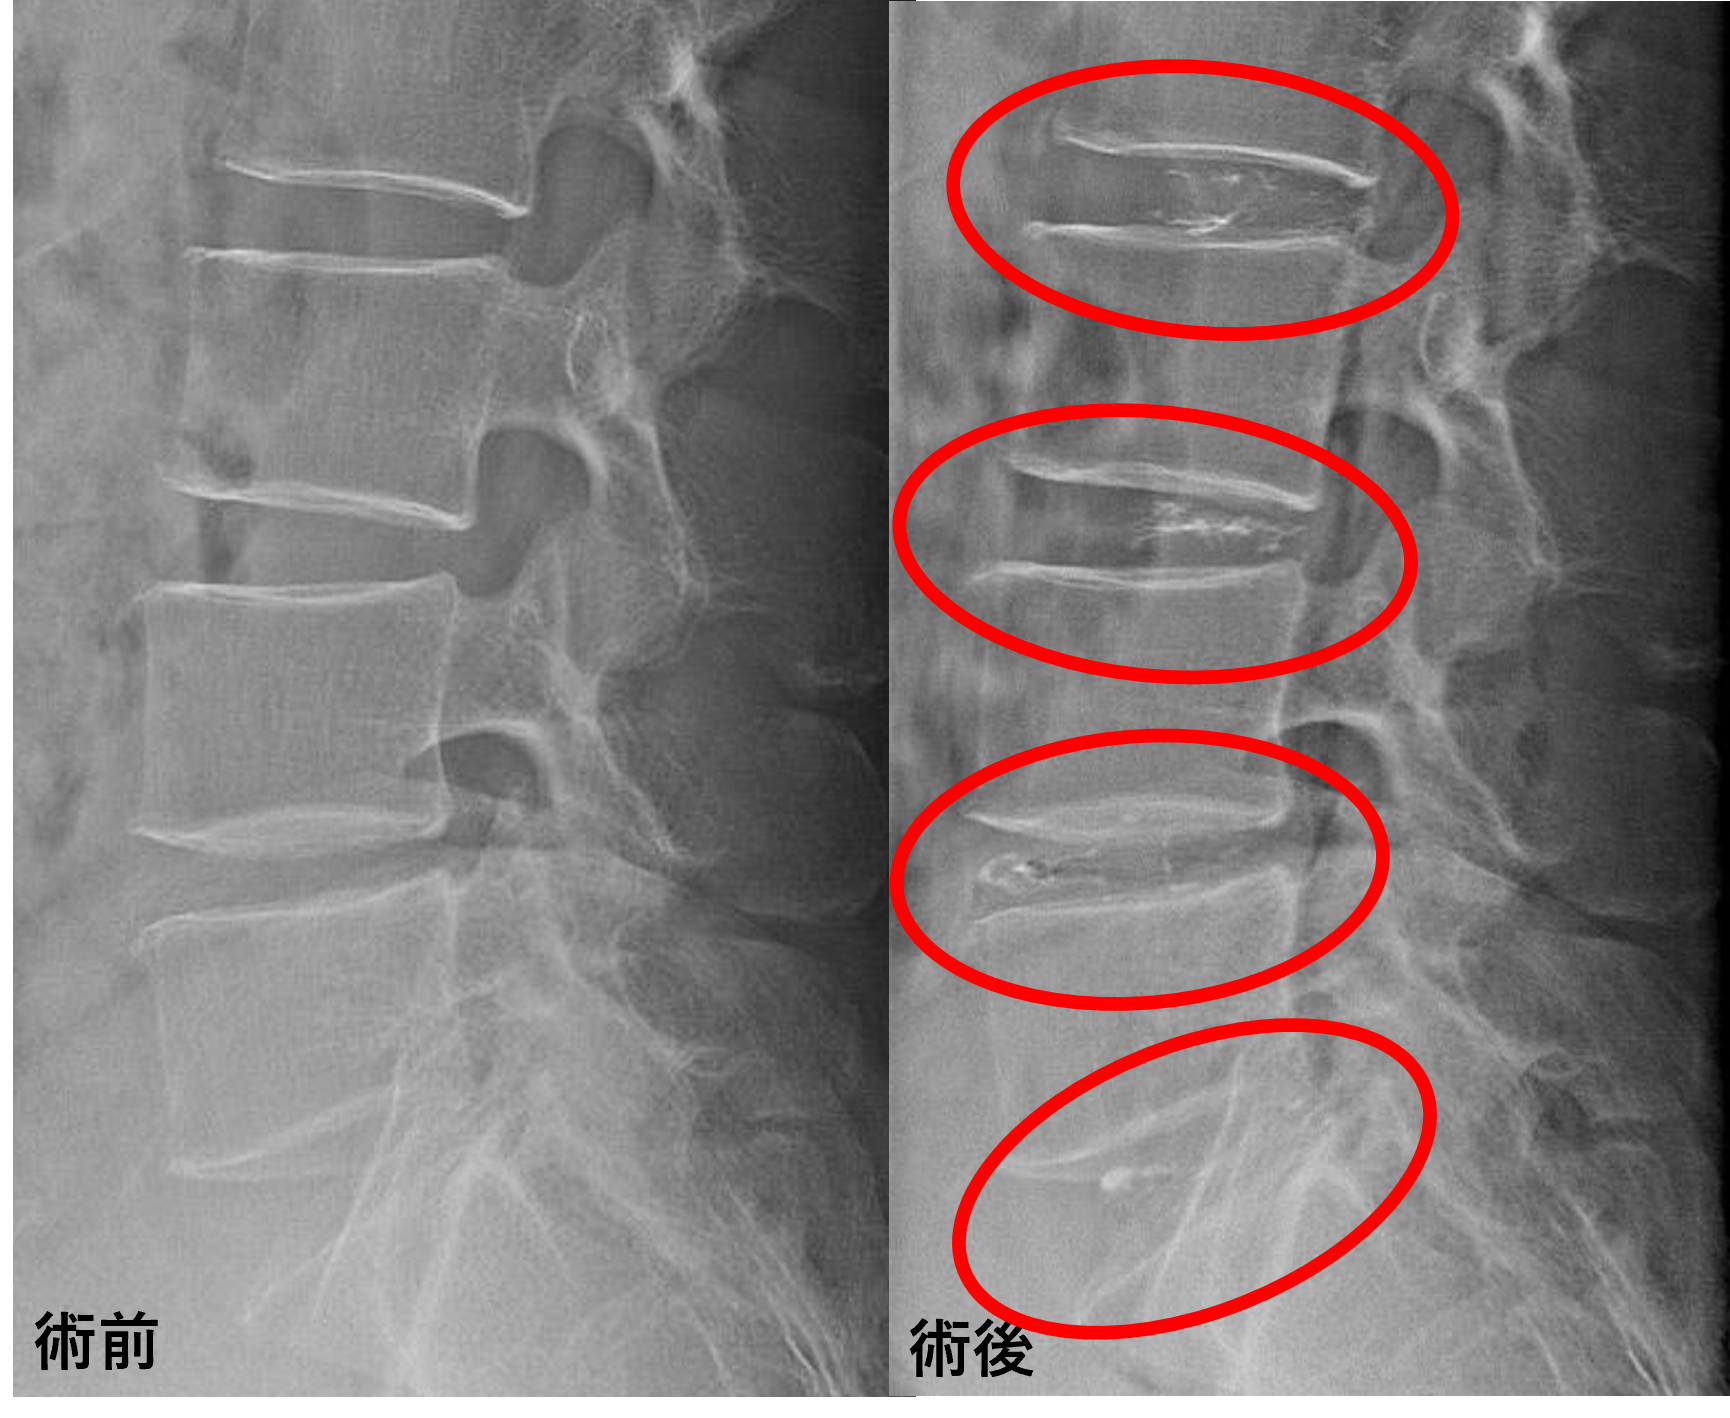

- L2/3、3/4、4/5 – 椎間板変性、膨隆

- L5/s – 椎間板変性、膨隆、繊維輪断裂

L2/3、3/4、4/5、5/sの椎間板所見による脊柱管の圧排が、症状の原因の可能性が高い。

患者様と相談の元、L2/3、3/4、4/5、5/sにセルゲル法を施行